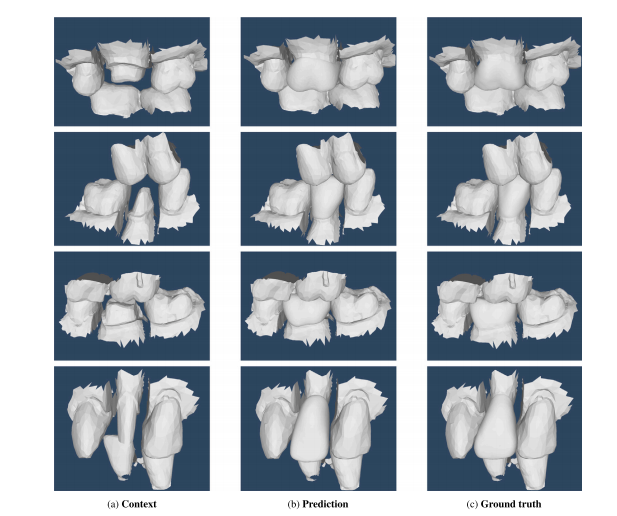

Fig. 6. Examples of mesh completions by the proposed architecture. (a) Input context containing master arch, prepped tooth and opposing arch; (b) Generated mesh in its context;(c) Ground truth mesh in its context

图6:由所提出的架构完成的网格补全示例。(a) 包含主牙弓、预备牙以及对颌牙弓的输入内容;(b) 在相应内容背景下生成的网格;(c) 在相应内容背景下的真实网格。